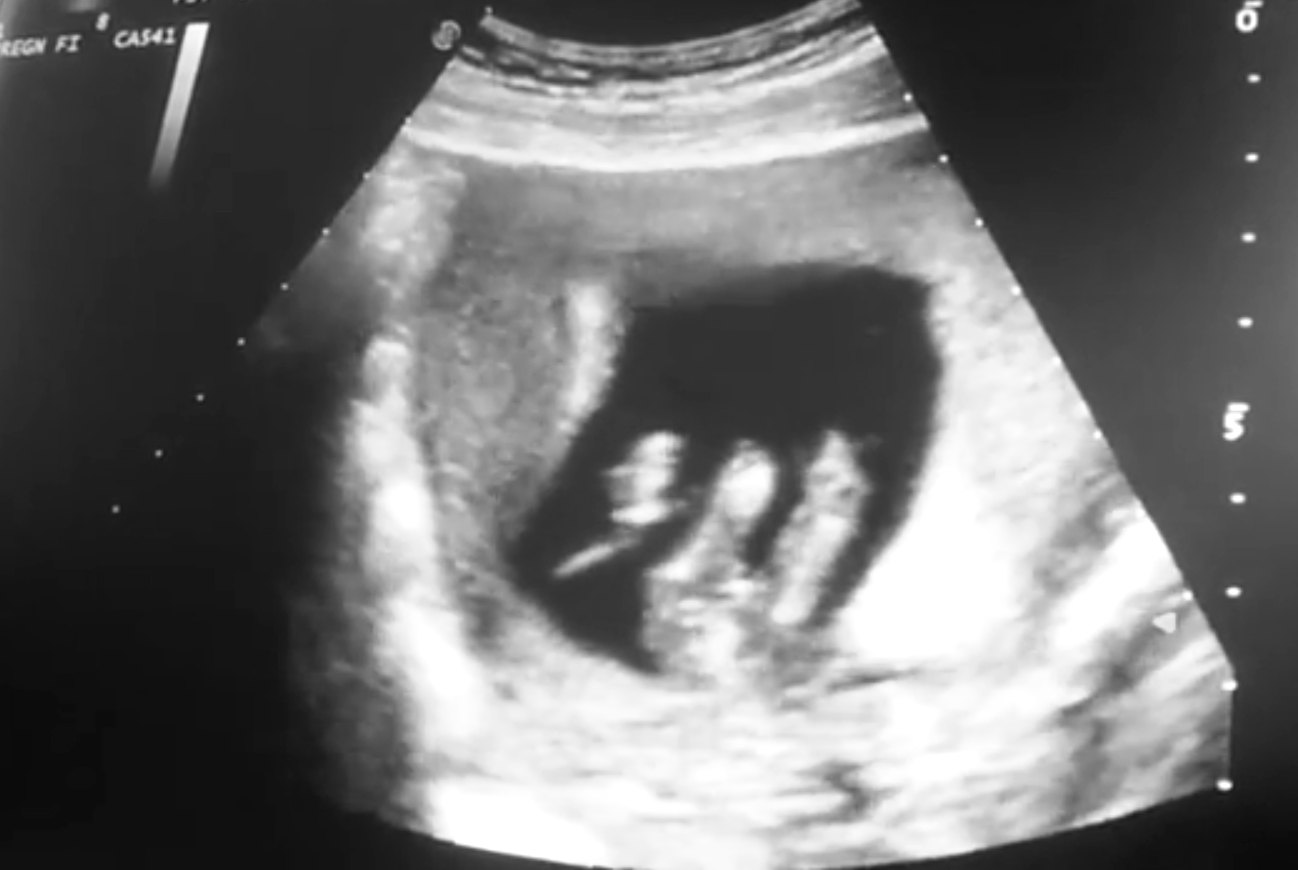

Hello! :D I am Stefania and i was hoping if someone can see/guess if i'll get a boy or a girl.

On the photos i am 14.5weeks. Thanks already!

Boy

I would guess boy

That's so tough I actually thought girl at first but going 50/50 x

For gestation, I would guess girl. I would think a boy would be 90 degrees up at this point. But it does have an angle. I can't say I am confident either way.